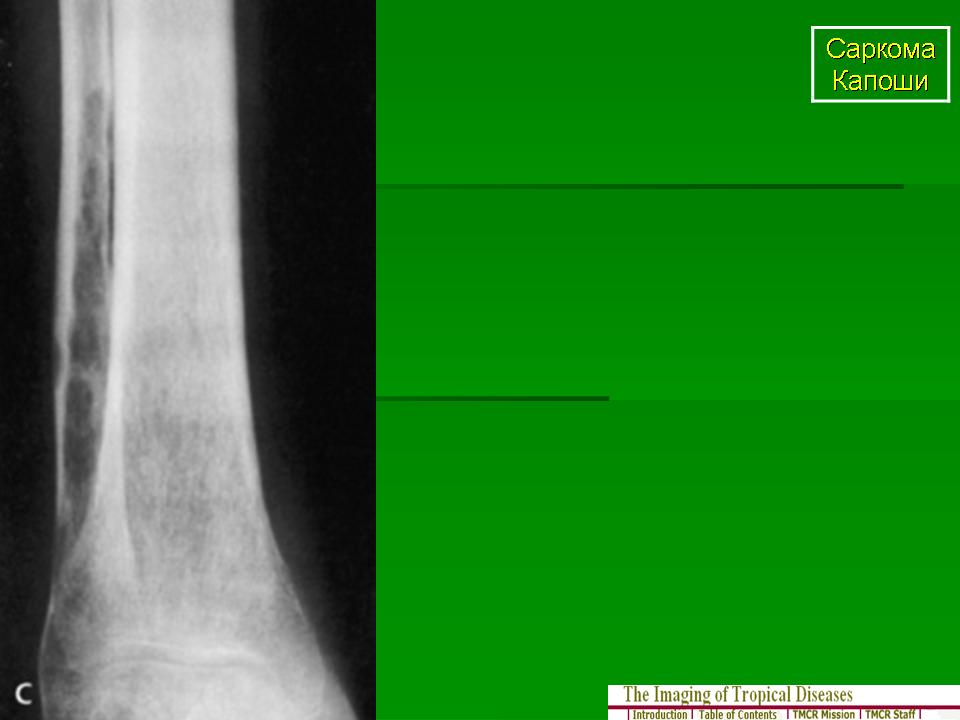

Саркома Капоши

Саркома Капоши — это многоочаговая злокачественная опухоль, которая поражает весь организм, происходит из эндотелия сосудов и обладает различным клиническим течением. Чаще всего болезнь проявляется поражением кожи, но способна затрагивать и слизистые оболочки, и лимфатическую систему, и внутренние органы (прежде всего легкие и ЖКТ). Описано четыре клинические формы саркомы Капоши: классическая (европейская), иммуносупрессивная, эндемическая (африканская) и эпидемическая (ассоциированная со СПИДом).